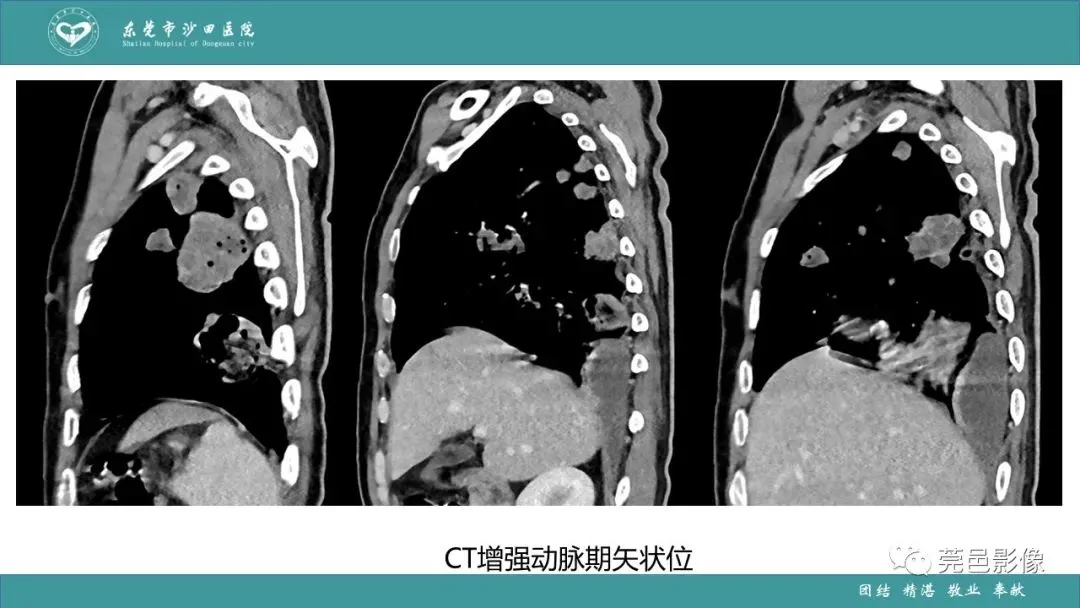

>课件 | 肺炎克雷伯杆菌肺炎影像学诊断与鉴别诊断

课件 | 肺炎克雷伯杆菌肺炎影像学诊断与鉴别诊断